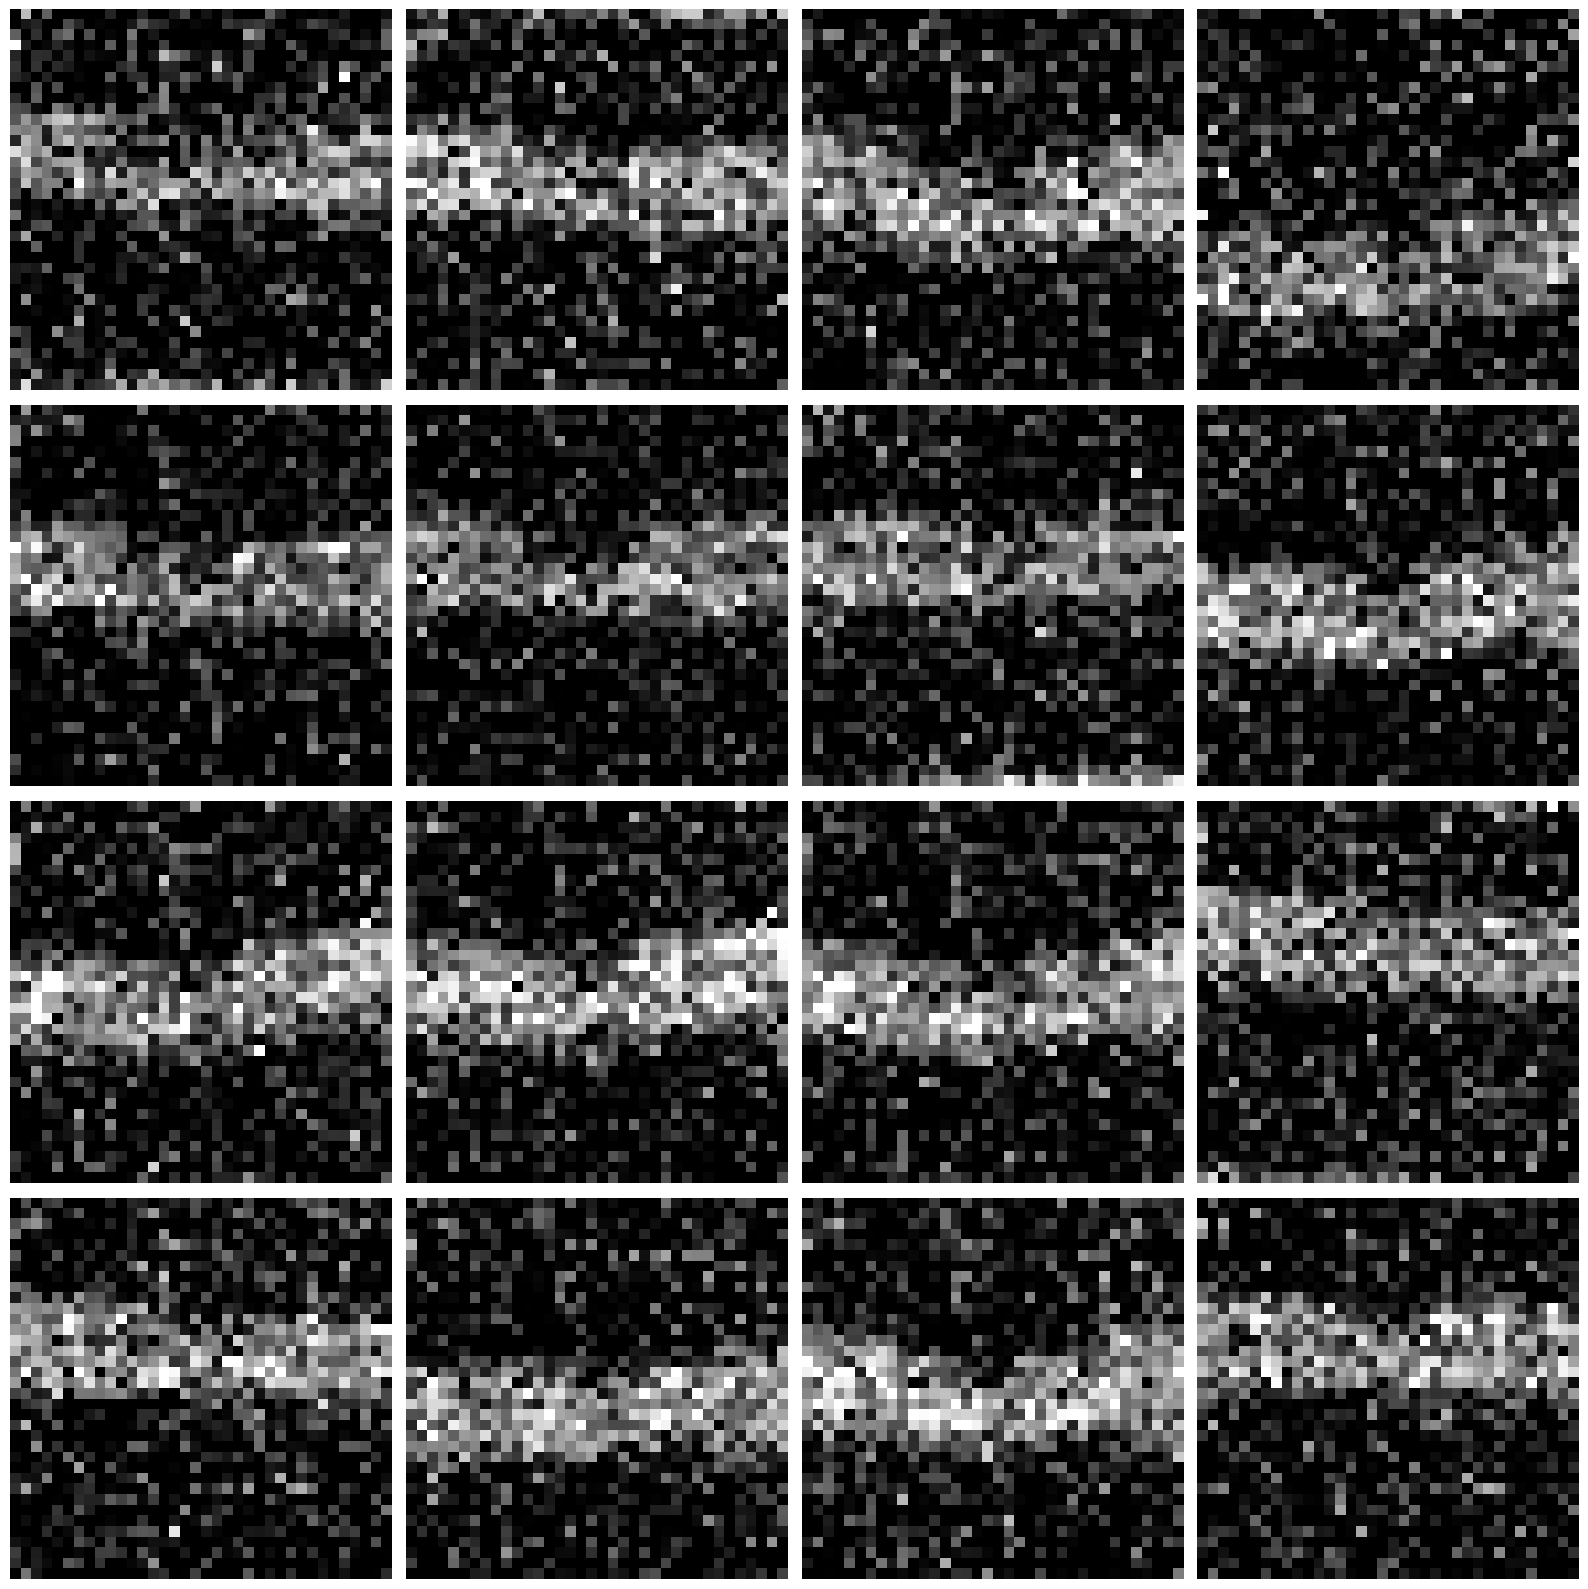

4.2. Results on OCTMNIST

OCTMNIST contains retinal OCT B-scans from the MedMNIST collection [80]. Unlike handwritten digits, medical images are generally less sparse. However, OCT exhibits banded anatomy: most diagnostic content concentrates in a narrow horizontal band (retinal layers) near the upper or middle part of the frame; while large regions, especially the lower half, are near-zero background (see Figure 2 for illustration). This induces substantial spatial sparsity, which is around 6570%65–70\% near-zero pixels at native resolution.

Refer to caption

Figure 2. Original OCTMNIST samples

Figure 3 shows CSDM generations at different compression levels. With low compression/high retention (76%76\%), the retinal band is continuous and well localized; intra-band texture appears with mild grain, and the background remains largely quiescent. Layer transitions are visible, with only light speckle around boundaries. With high compression/low retention (34%34\%), the band stays recognizable and contiguous, yet shows higher intra-band speckle and occasional softening at sharp transitions; background grain is more pronounced. Overall, CSDM preserves the banded retinal anatomy, while delivering substantial wall-clock savings. Artifacts concentrate as mild speckle and slight softening within the band at aggressive compression, but the decision-relevant structure (e.g., band continuity and localization) remains clear across settings.